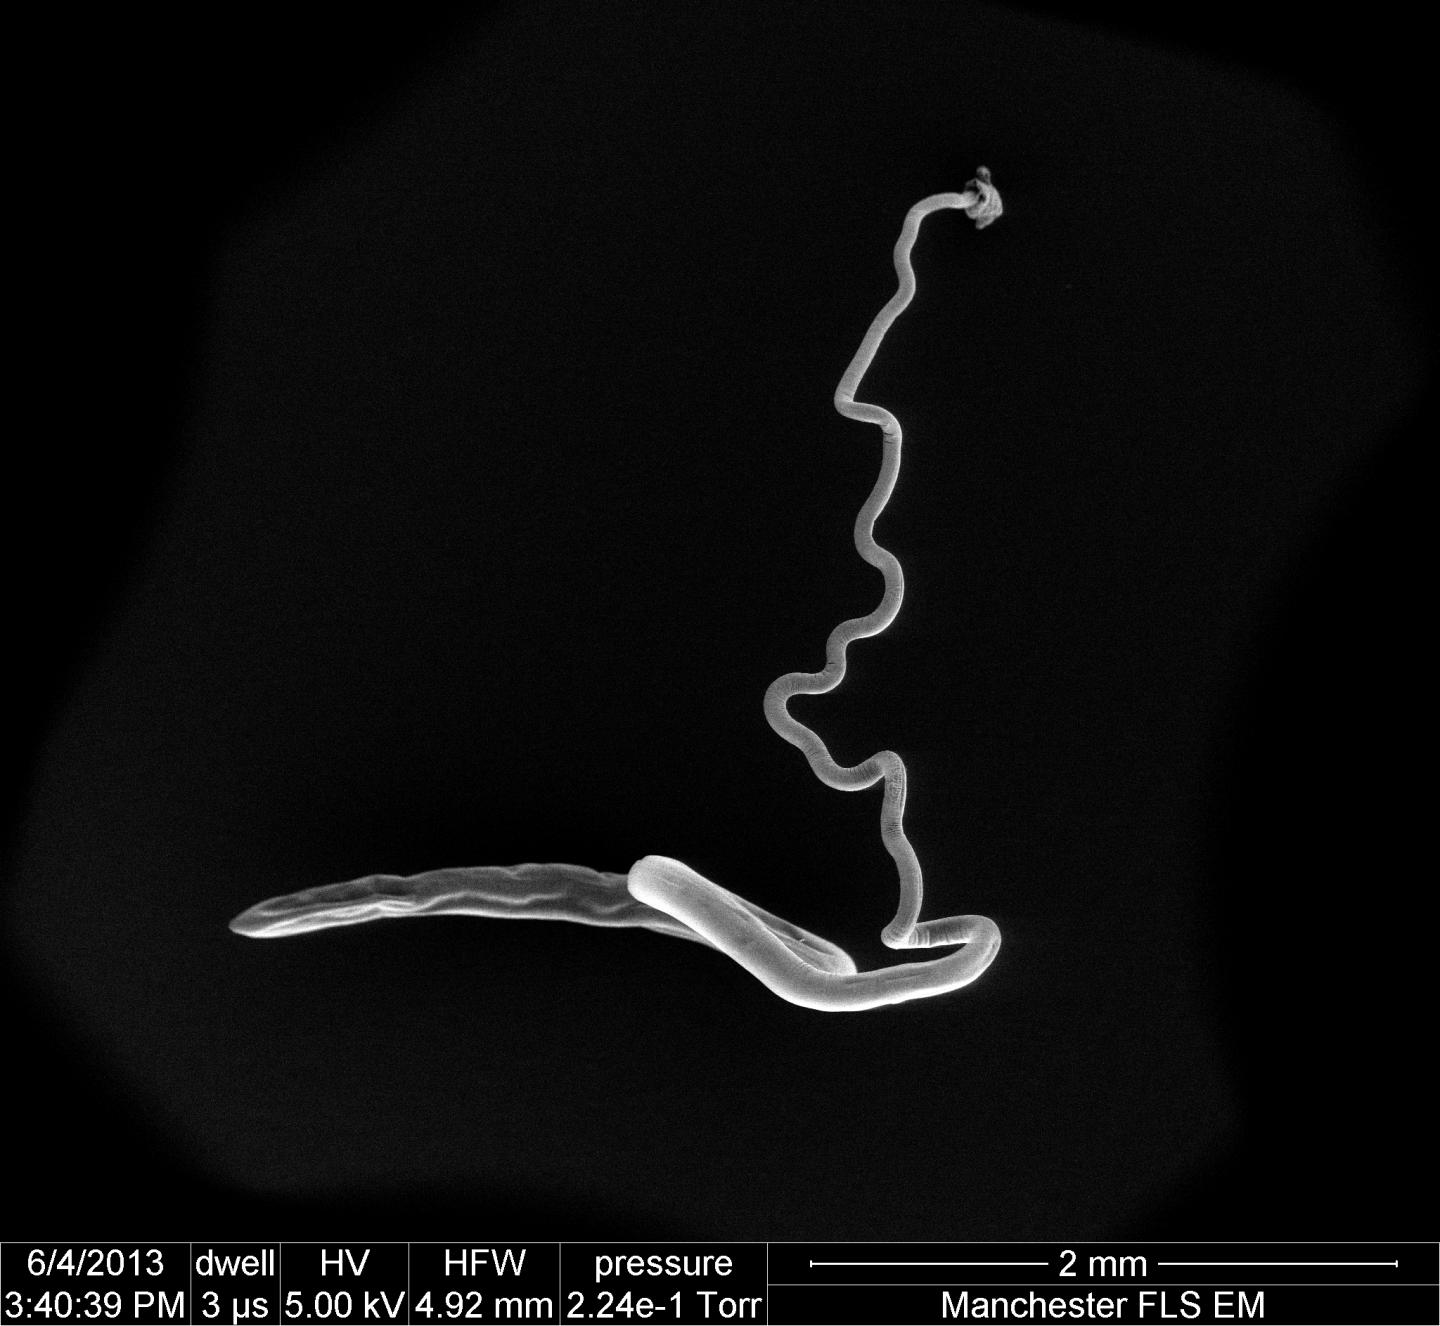

Whipworm, gets its name because it resembles a whip and causes the disease known as trichuriasis. Infection develops after ingesting whipworm eggs from the contaminated soil.

According to the team, the bacteria found in the 2 cm long worm's gut are unexpectedly different from the gut in which they live.

Intriguingly, we also were able to show that the parasites themselves have their own microflora within their own intestines. Interestingly and surprisingly, the bacterial populations found in the worm's gut are very different from the gut of the host in which they live. So they change the host gut bacteria to enhance their own survival but need to keep a "good" population of bacteria for their own health. Indeed, without the bacteria in the worms' gut, the worms cannot grow and thrive.